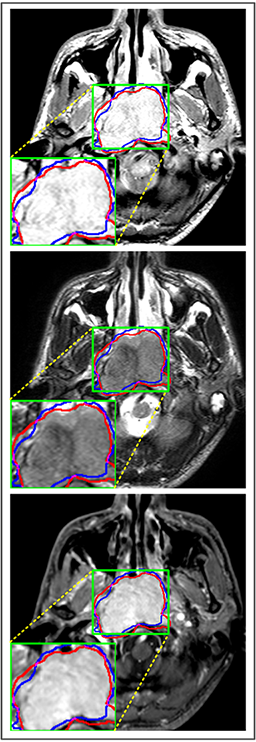

Comparison with ground truth. Some predicted results of MMFNet are shown in 2D images and 3D images in Figure 7 and Figure 8. As shown in these figures, although the shape and size of NPC are varied from each other, MMFNet can still accurately determine the regions of NPC and obtain the accurate contours of tumors. Through analyzing 2D images in figure 7, MMFNet has a capacity to fuse multi-modality MRI to reduce the confusion brought by intensity’ similarity between nearby tissues and NPC. The values of , and of MMFNet are shown in Table 1. MMFNet can reach the best results with , and .

Comparison with related works. Table 1 reports the values of , and for different methods. Predicted masks of different methods are illustrated in Figure 9 and Figure 10, which respectively present results in 2D and 3D images. Through comprehensively analyzing these results, the proposed MMFNet actually have the following properties:

(i) It directly fuses 3D MRI images rather than 2D slices. Thus, it can effectively use meaningful information from neighboring slices of MRI to realize NPC segmentation. As shown in Table 2, MMFNet can bring , and improvements in and compared to the best method based on 2D images (Multi-modality patch-based CNN). And Figure 10 shows that 3D-based methods have less isolated regions (false positives) than 2D-based ones.

(ii) It segments NPC by fusing multi-modality MRIs with the multi-encoder network. Thus, it can learn complementary and interdependent features from different modalities of MRI for final decisions. Additionally, comparing with input-level fusion networks and decision-level fusion networks, layer-level fusion networks (including MMFNet) can effectively capture informative features from different modalities of MRI and fuse low-level features and high-level features.

(iii) It uses a fusion block to fuse low-level features from different modalities of MRI and prepare these low-level features for the fusion with high-level features. Thus, it can more effectively fuse information from various sources. It also uses the self-transfer strategy to initialize the netwerk. Hereby, it can stimulate encoders to make full mining of meaningful features from modality-specific MRI. And it finally improve base multi-encoder-based network (Merging encoders’ fetures) by , and in and .